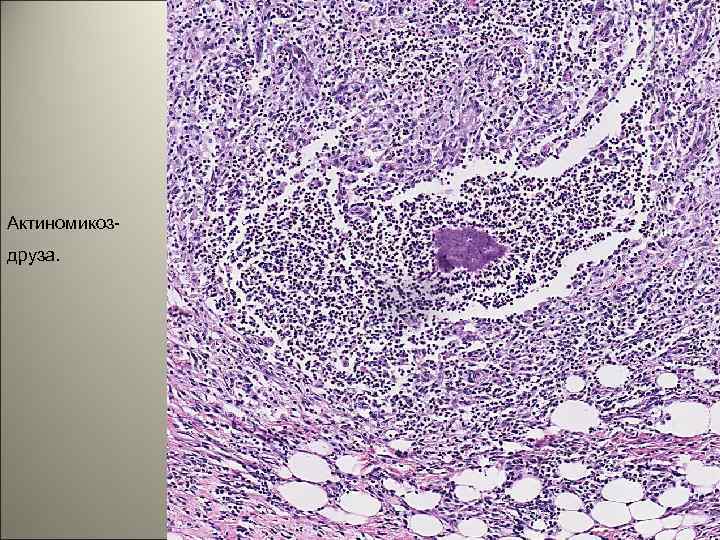

Актиномикоздруза. 49

• Актиномикоз (actinomycosis) — висцеральный микоз, возникающий в результате внедрения в организм актиномицетов. • Актиномикоз является хроническим гранулематозным заболеванием, которое обычно вызывает нагноение и формирование абсцесса, а также имеет тенденцию образовывать свищевые ходы. • Поражаются любые органы и ткани, но чаще область лица, шеи, челюстей. Заболевают преимущественно мужчины, в основном городские жители. 45

• В настоящее время установлено, что возбудителями актиномикоза являются грамположительные бактерии — микроаэрофильные, аэробные и анаэробные актиномицеты, которые широко распространены в природе. 47